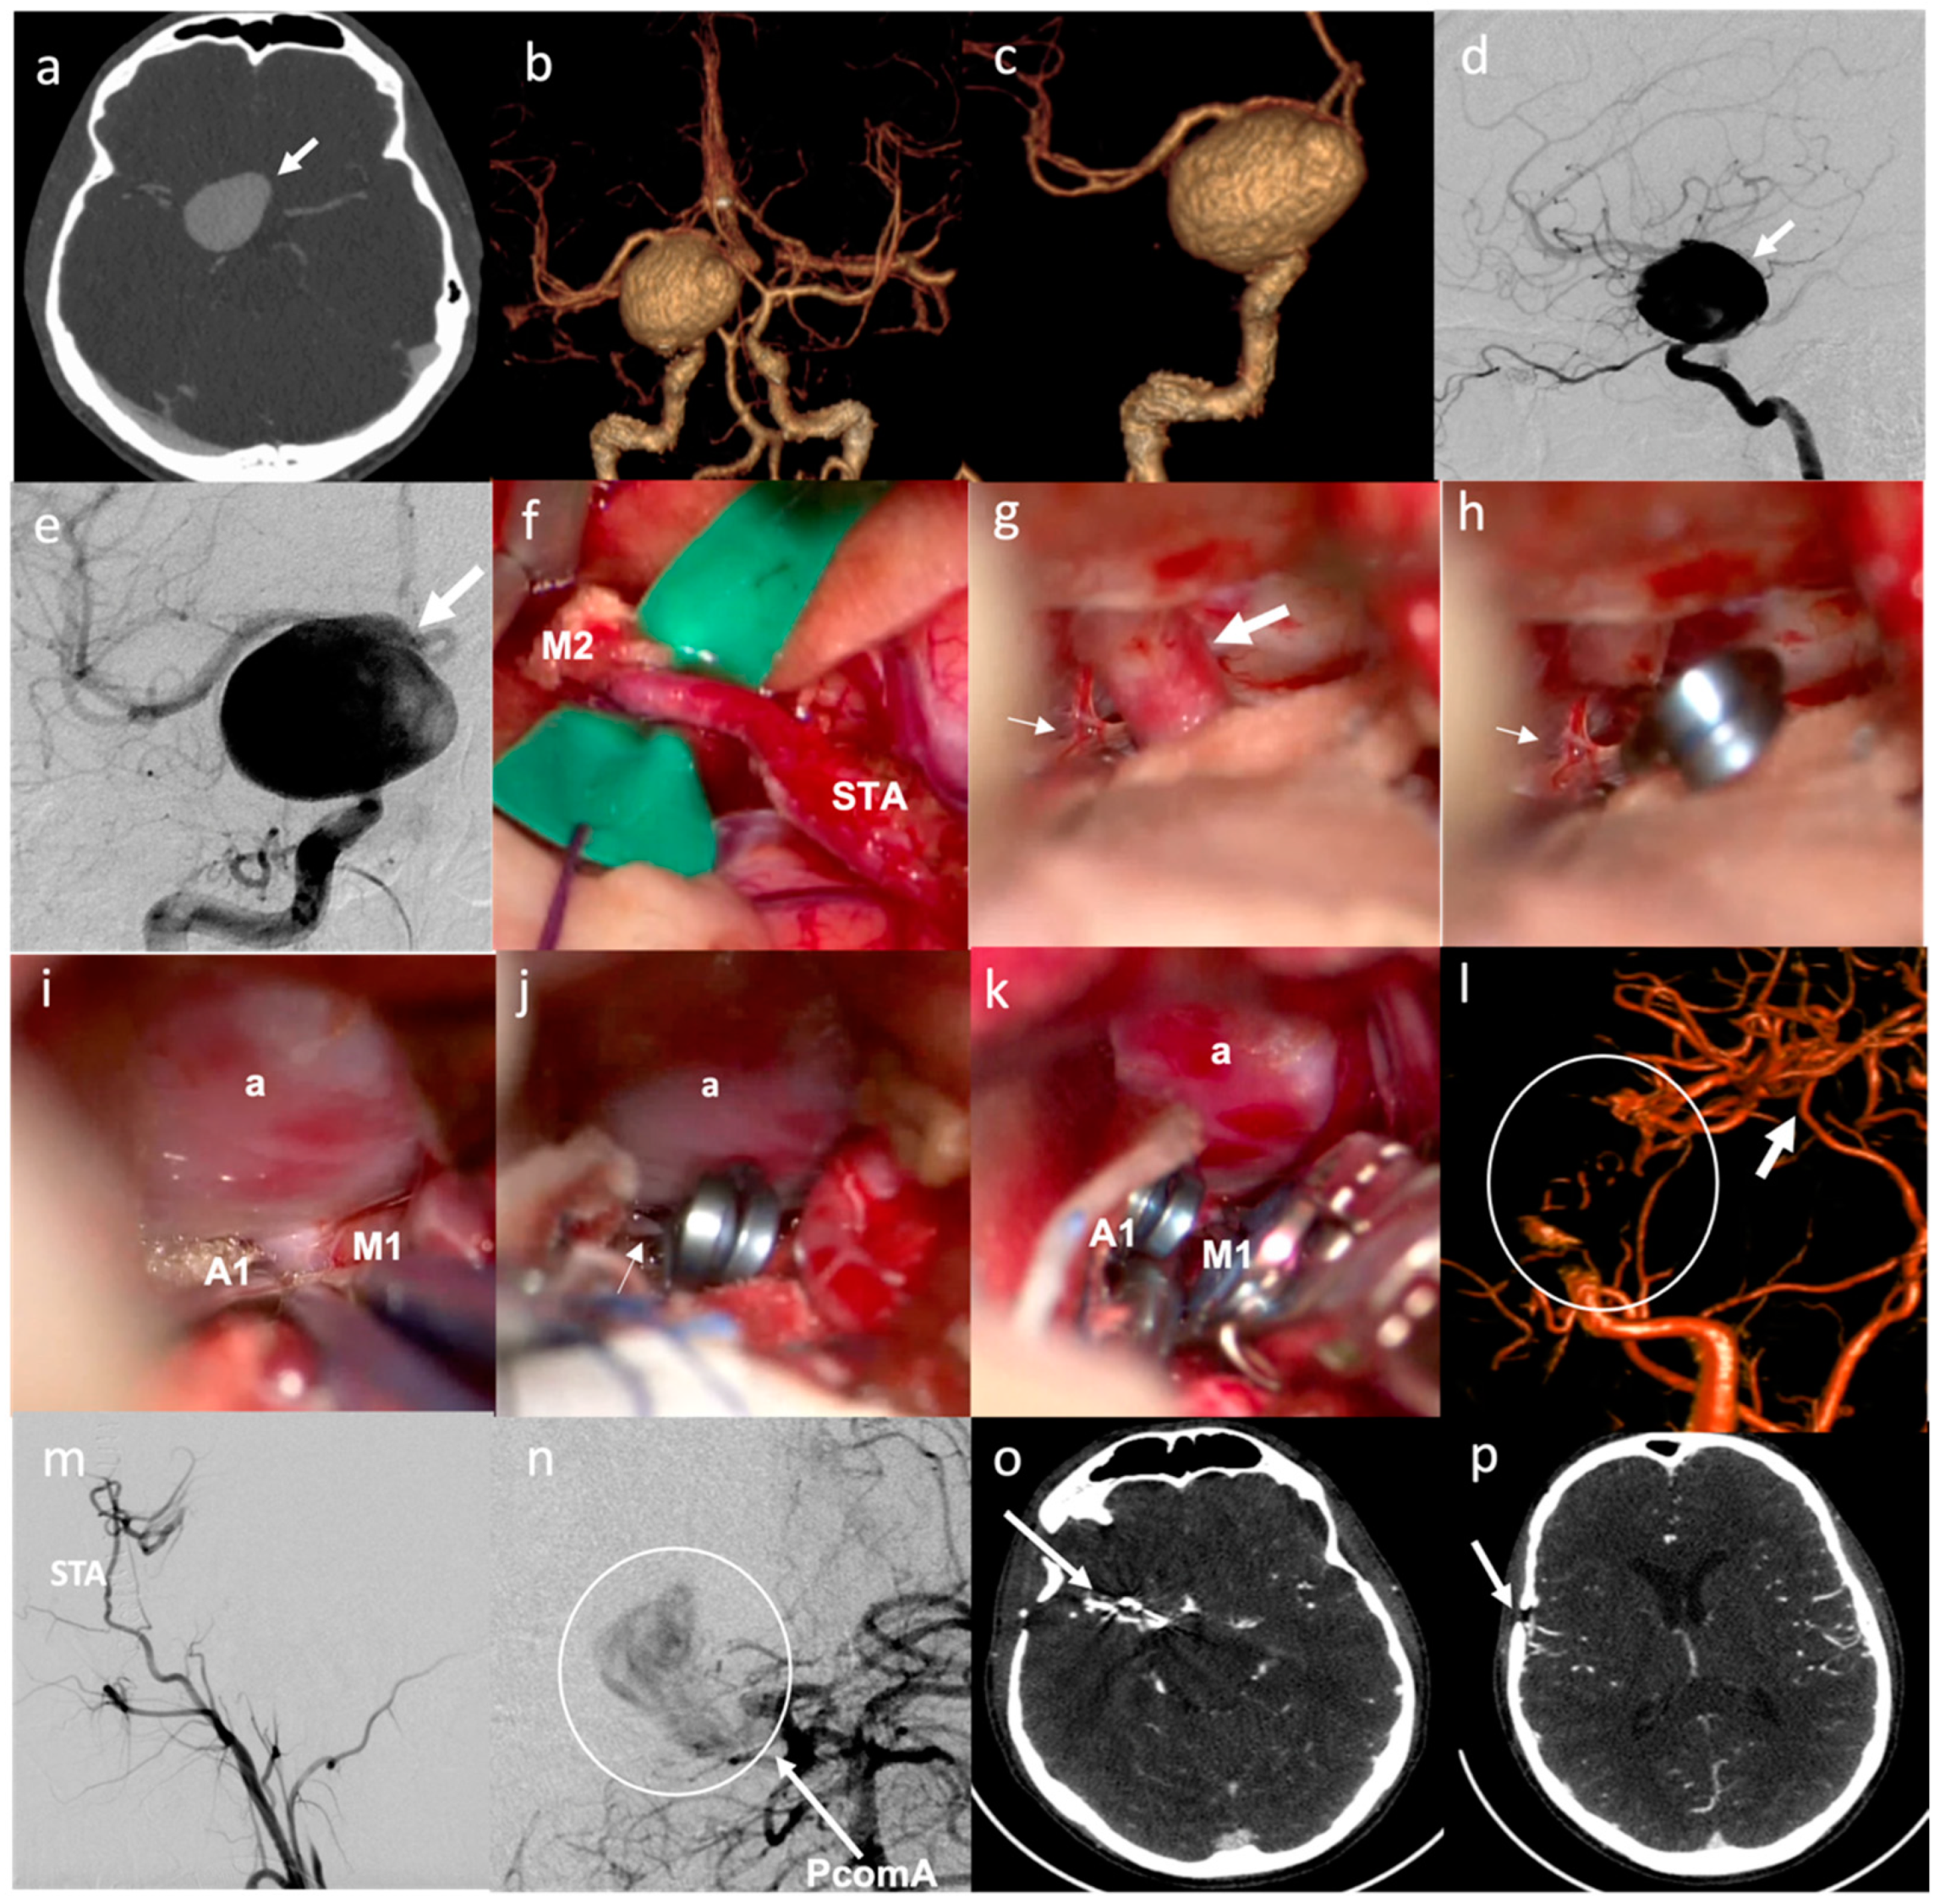

- In six patients, a simple STA–MCA bypass was performed. In two cases (patients no. 2 and 17), this type of bypass was performed to replace a single MCA branch involved in the aneurysm sac as part of the occlusion strategy (Figure 1). In two cases (patients no. 19 and 20), STA–MCA bypasses were performed after having addressed a partially thrombosed aneurysm of the MCA with a temporary clipping, removal of the thrombus and clip reconstruction, with ICG videoangiographic evidence of occlusion of an MCA branch coming out from the aneurysm sac; in these cases, the parietal branch of the STA had been prepared at the beginning of surgery to be ready in case a bypass was needed. In one case (patient no. 6), the patient presented a giant, partially thrombosed and calcified aneurysm of the left ICA, compressing the M1 tract of the left MCA, with a resultant hypoperfusion in the MCA territory and recurrent transient ischemic attacks (TIAs); the STA–MCA bypass was therefore performed to correct the hypoperfusion in the MCA territory before endovascular occlusion of the ICA aneurysm (Figure 2). In one case (patient no. 22), the patient presented a giant aneurysm of the supraclinoid prebifurcation ICA, and the STA–MCA bypass was used to replace flow in the MCA territory before partial trapping of the aneurysm, taking into consideration that flow in the ACA territory was assured by a large AcommA (Figure 3).